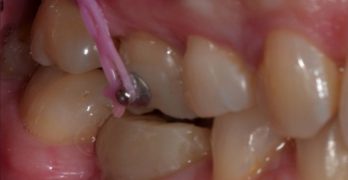

Pistol Spring: La Innovadora Solución para Corregir Molares Ectópicos en Niños

Para comenzar nuestra semana traemos un artículo llamado The ‘pistol spring’ for correcting ectopic permanent molar … [Leer más...] acerca de Pistol Spring: La Innovadora Solución para Corregir Molares Ectópicos en Niños